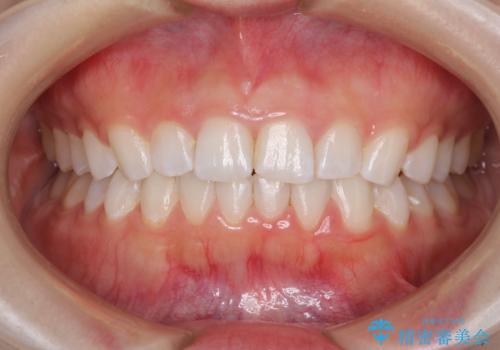

デコボコと深い咬み合わせの改善 インビザラインによる矯正治療

- 口元のデコボコと深い咬み合わせ(ディープバイト)を気にして来院された患者様です。

インビザラインによる上下歯列の拡大と、IPR(歯と歯の間を削る)にるスペースの獲得により、口元のデコボコとディープバイトを改善することとしました。

インビザラインは、装着していない時間がどれだけ短いかが、治療期間を大きく左右します。こちらの患者様は1日22時間以上、毎日欠かさず装着してくださったため、1年強という短期間で満足のいく歯列に整えることができました。